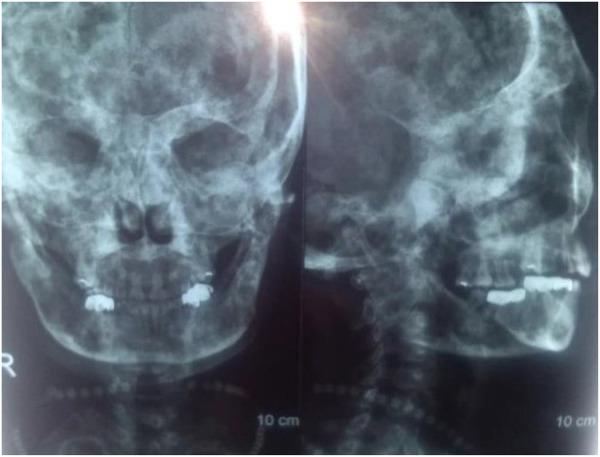

患者2009年至2013年间接受了四次静脉输注唑来膦酸5mg,同时口服补钙。2010年7月进行右侧全髋关节置换术(THA)。术后髋关节X线片见图1。碱性磷酸酶和骨钙素水平分别为538 IU/L和192.5 ng/ml。2013年12月,患者接受了矫形外科手术和右髁上截骨(图2)。入院时,碱性磷酸酶和骨钙素水平为403 IU/L和246.30 ng/ml。2015年5月,患者因跌倒导致左股骨干骨折,并接受了钢板和螺钉内固定(图3)。根据术后组织病理学,最终诊断为纤维发育不良。2015年12月,移除右侧股骨板,以防止应力集中和随后的股骨干骨折。尽管患者在随访期间没有出现明显并发症,但于2017年和2018年在另一家医院接受了颌下感染和下颌骨坏死的治疗(图4)。

图4 下颌骨坏死的X光片